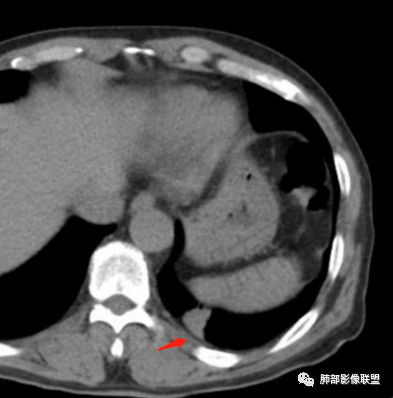

糊墙,胸膜下脂肪间隙明显增厚

边缘平直为主,部分膨隆,糊墙征

2、影像表现:无肺气肿背景、定位左肺下叶后基底段,不规则结节、与支气管关系不明确,部分边缘平直、部分膨隆,病变与胸膜宽基底相连,病变与胸膜糊墙征,病变周围见细、长、软毛刺,病变密度比较均匀。影像总体倾向炎症、符合肺组织慢性炎症伴机化。

6.观察结节和(或)肿块的邻近结构:邻近气道的截断常见于肺癌;邻:近血管集束征可见于肺癌及炎性病变;邻近结构的侵犯常见于恶性肿瘤;邻近胸膜凹陷征常见于肺癌。